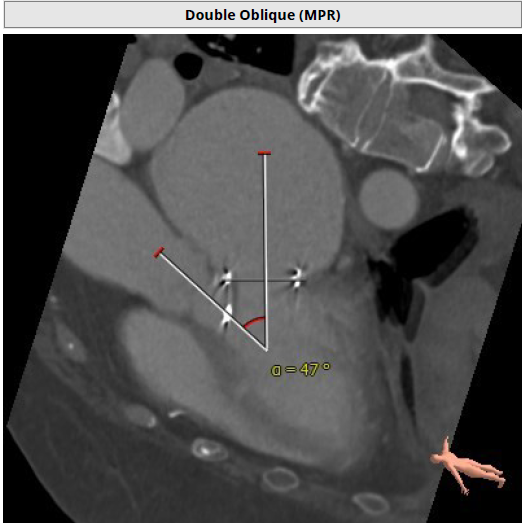

2. AV-MV double S curve :RAO 42°/ CAU 47°,此角度为二尖瓣主动脉瓣最佳观察位;

3. 左心室和二尖瓣轴线角度:146°;